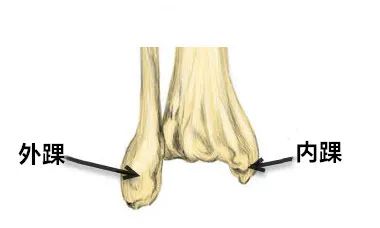

体上、中1/3交界处附近,有向上开口的滋养孔。胫骨下端稍膨大,其内下方的突起称内踝。下端的下面和内踝的外侧面有关节面与距骨相关节。下端的外侧面有腓切迹与腓骨相接。内踝可在体表扪到。